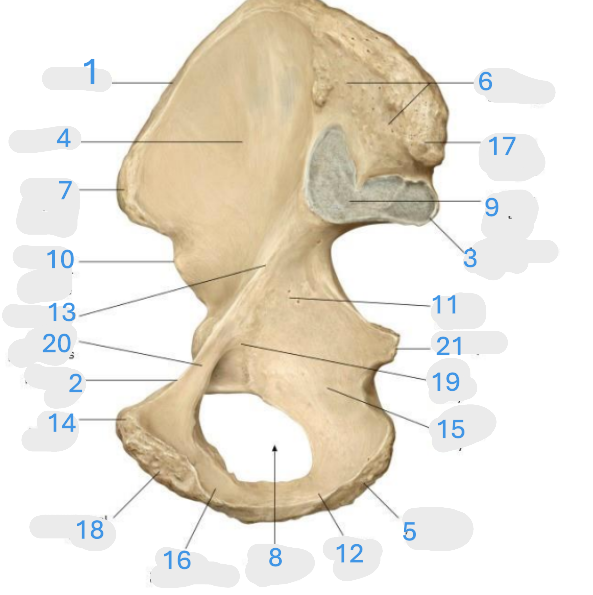

Where is the iliac crest

1

Where is the pectineal line

2

Where is the posterior iliac spine

3

Where is the iliac fossa

4

Where is the ischial tuberosity

5

Where is the iliac tuberosity

6

Where is the anterior superior iliac spine

7

Where is the obturator foramen

8

Where is the auricular surface of the ilium

9

Where is the anterior inferior iliac spine

10

Where is the ilium body

11

Where is the ischial ramus

12

Where is the arcuate line

13

Where is the pubic tubercle

14

Where is the ischium body

15

Where is the inferior pubic ramus

16

Posterior superior iliac spine

17

Where is the symphyseal surface

18

Where is the pubis body

19

Where is the superior pubic ramus

20

Where is the ischium body

21